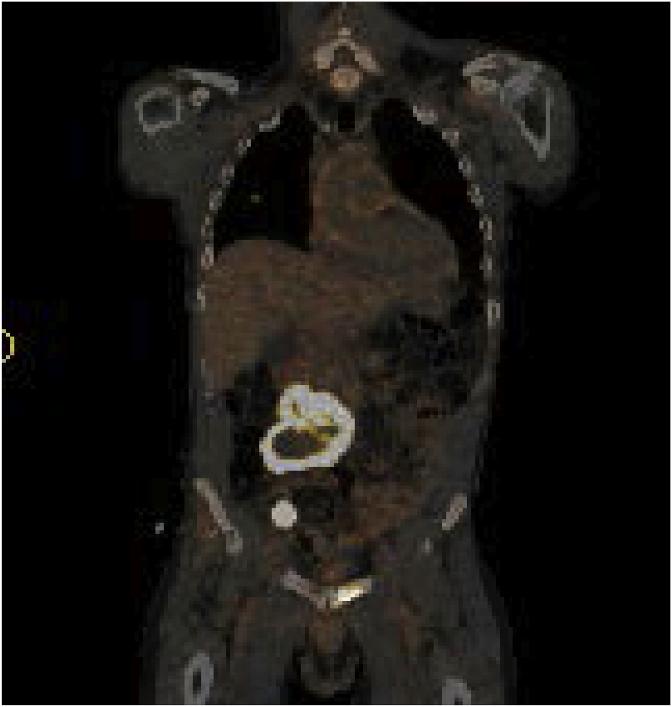

Primary angiosarcoma of the testis with retroperitoneal metastasis.

Urol Case Rep. 2018 Sep 19;21:116-118. doi: 10.1016/j.eucr.2018.09.014. eCollection 2018 Nov.